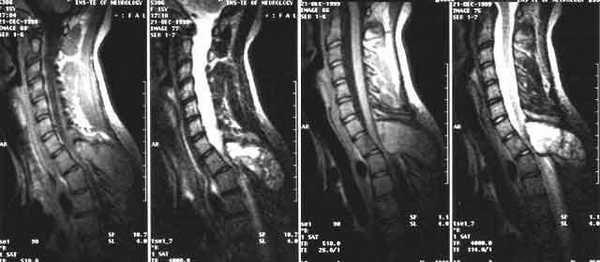

3. Магнитно-резонансная томография (МРТ) с контрастным усилением. На данный момент это основной метод диагностики новообразований спинного мозга. МРТ позволяет визуализировать весь спинной мозг и позвоночник и определить локализацию опухоли. Накопление контрастного вещества определяет не только распространение, но и гистологическую структуру опухоли [5] [6] .

4. КТ-миелография. Применяют для выявления границ опухоли. Метод заключается в контрастировании субарахноидального пространства (полости со спинномозговой жидкостью между мягкой и паутинной оболочками спинного мозга) водорастворимыми веществами. В комбинации с МРТ или КТ позволяет значительно улучшить диагностику опухолей спинного мозга, особенно в окружающих его тканях.